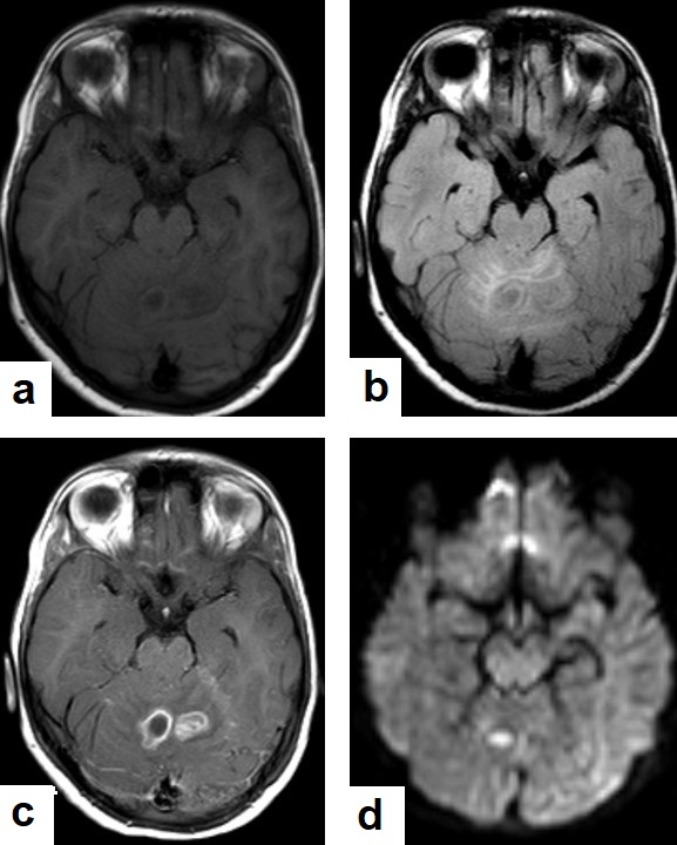

Figure 16. Tuberculous abscess in the right cerebrum of a 13-year-old female. Selected images of brain MRI (a) T1-weighted image (WI), (b) T2-WIs, (c) T1-WI with contrast, and (d) FLAIR-WI. The images show a well-defined lesion in the right cerebral hemisphere with low-signal-intensity content and a high-signal-intensity capsule on T1WI, which appear as high-signal-intensity content and a low-signal-intensity capsule on T2WI (b); there is marginal enhancement on T1WI with contrast administration (c), and there are low-signal-intensity contents and a high-signal-intensity capsule on FLAIR (d). Obvious grade-2 vasogenic oedema around the lesion on T2WI and FLAIR.

Figure 17. A tuberculous abscess in the cerebellum of a 13-year-old female (same patient as Figure 16). Selected images of brain MRI (a) T1-weighted image (WI), (b) FLAIR-WIs, (c) T1-WI with contrast, and (d) diffusion-weighted (DW) image. The images show a well-defined lesion in the cerebellum with low signal intensity content and a high signal intensity capsule on T1WI and FLAIR (b), marginal enhancement on T1WI with contrast administration (c), and restricted diffusion on DWI (d).